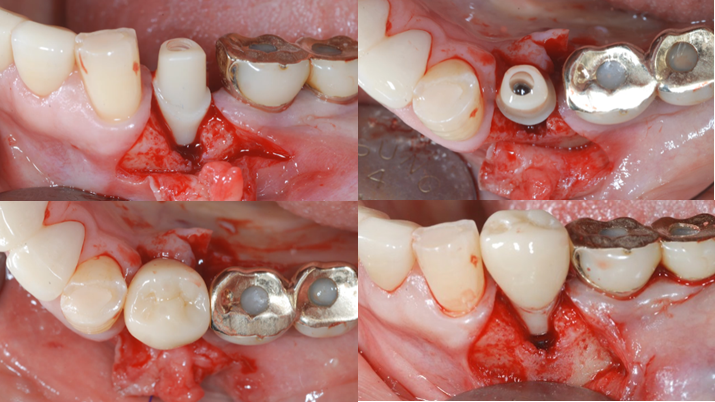

Clinical case: : Immediate loading of lower molars using R2Gate prefabricated 3D-printed provisional restoration

- Courtesy of Dr. Sam Omar, Egypt -

Keywords

Dr.Sam Omar, immediate loading, digital guided surgery, digital ONE-DAY implant, maxillary anterior, #21, guided surgery, immediate loading, AnyRidge, R2GATE, Mega ISQ, MEG Torq, R2GATE Full Surgical Kit

Products:

implant system, R2GATE Guide, R2GATE surgical kit (AnyRidge), Mega ISQ

“ONE-DAY implant, one-day smile

”